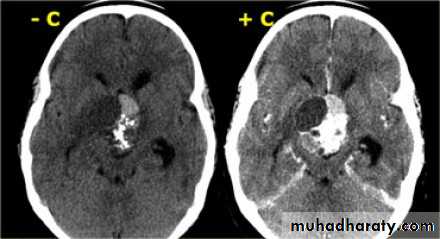

Glioma

Comments primary interracial tumor , vary greatly in malignancy , have many names depending on the histological type :

gliobtastoma multiforme G IV highly malignant t. named also as butterfly G. arise from the anterior or posterior aspect of the corpus callosum , extend & spread to both cerebral hemispheric sides

associated hemorrhage , necrosis , & cystic formation

IV( glioblastoma multiforme ) are highly malignant have all previous mentioned features .